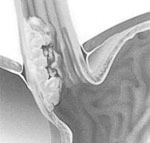

Лёгкие – рак лёгкого

У курильщиков с 20-тилетним стажем риск развития рака лёгкого на 60-70% выше, чем у некурящих. У 85% пациентов с раком лёгкого – заядлые курильщики. На формирование опухоли в лёгких оказывает влияние стаж курения, количество выкуриваемых сигарет и концентрация никотина и смол в сигаретном дыме. Симптомы рака лёгкого: одышка, мучительный кашель, кровохаркание, боль в груди, часто повторяющиеся пневмонии.

На представленном рентгеновском снимке отчётливо видно округлое патологическое образование, которое и является опухолью лёгких. Биопсия подтвердила злокачественность новообразования.